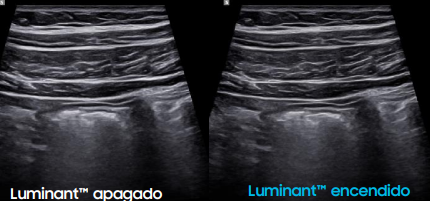

Calidad de Imagen Superior: Claridad, Profundidad y Precisión

El Samsung R20 ofrece tecnologías que garantizan imágenes nítidas, uniformes y de alto contraste en todo momento:

Gracias a estas tecnologías, el R20 garantiza diagnósticos visuales precisos incluso en estructuras complejas o difíciles de visualizar.